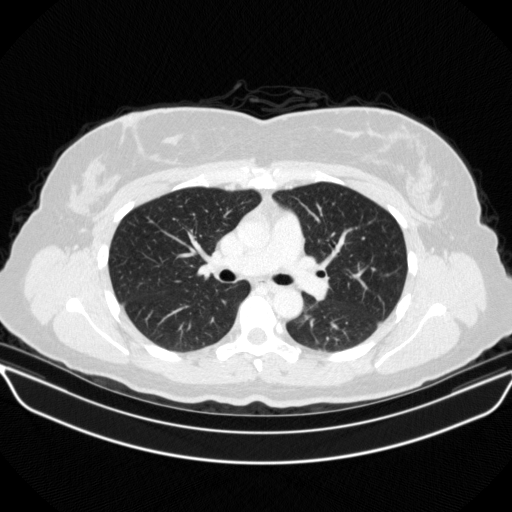

Original NATIVE CT scan (input)

Full window (WL 1023.5, WW 4095 β†’ Low βˆ’1024, High +3071)

Lung window (WL -600, WW 1500 β†’ Low βˆ’1350, High +150)

Mediastinum window (WL 40, WW 400 β†’ Low βˆ’160, High +240)